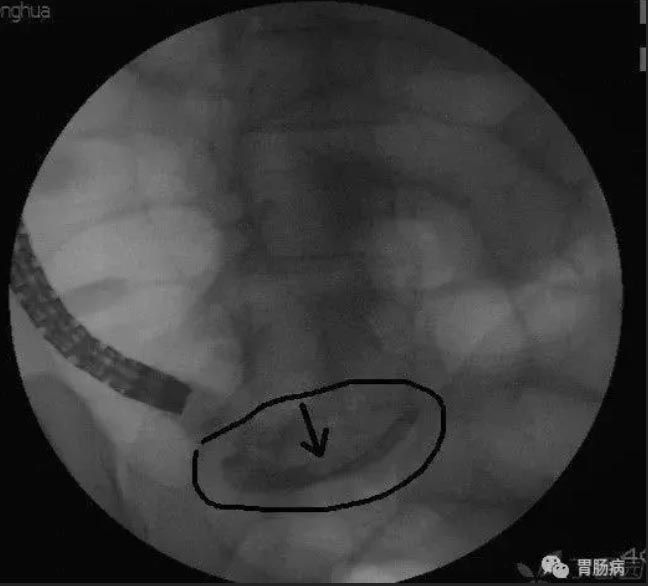

(4) Lithotomy by balloon or basket

The stercorolith was removed by balloon catheter or stone basket. The black arrow indicates that stercorolith was taken out.